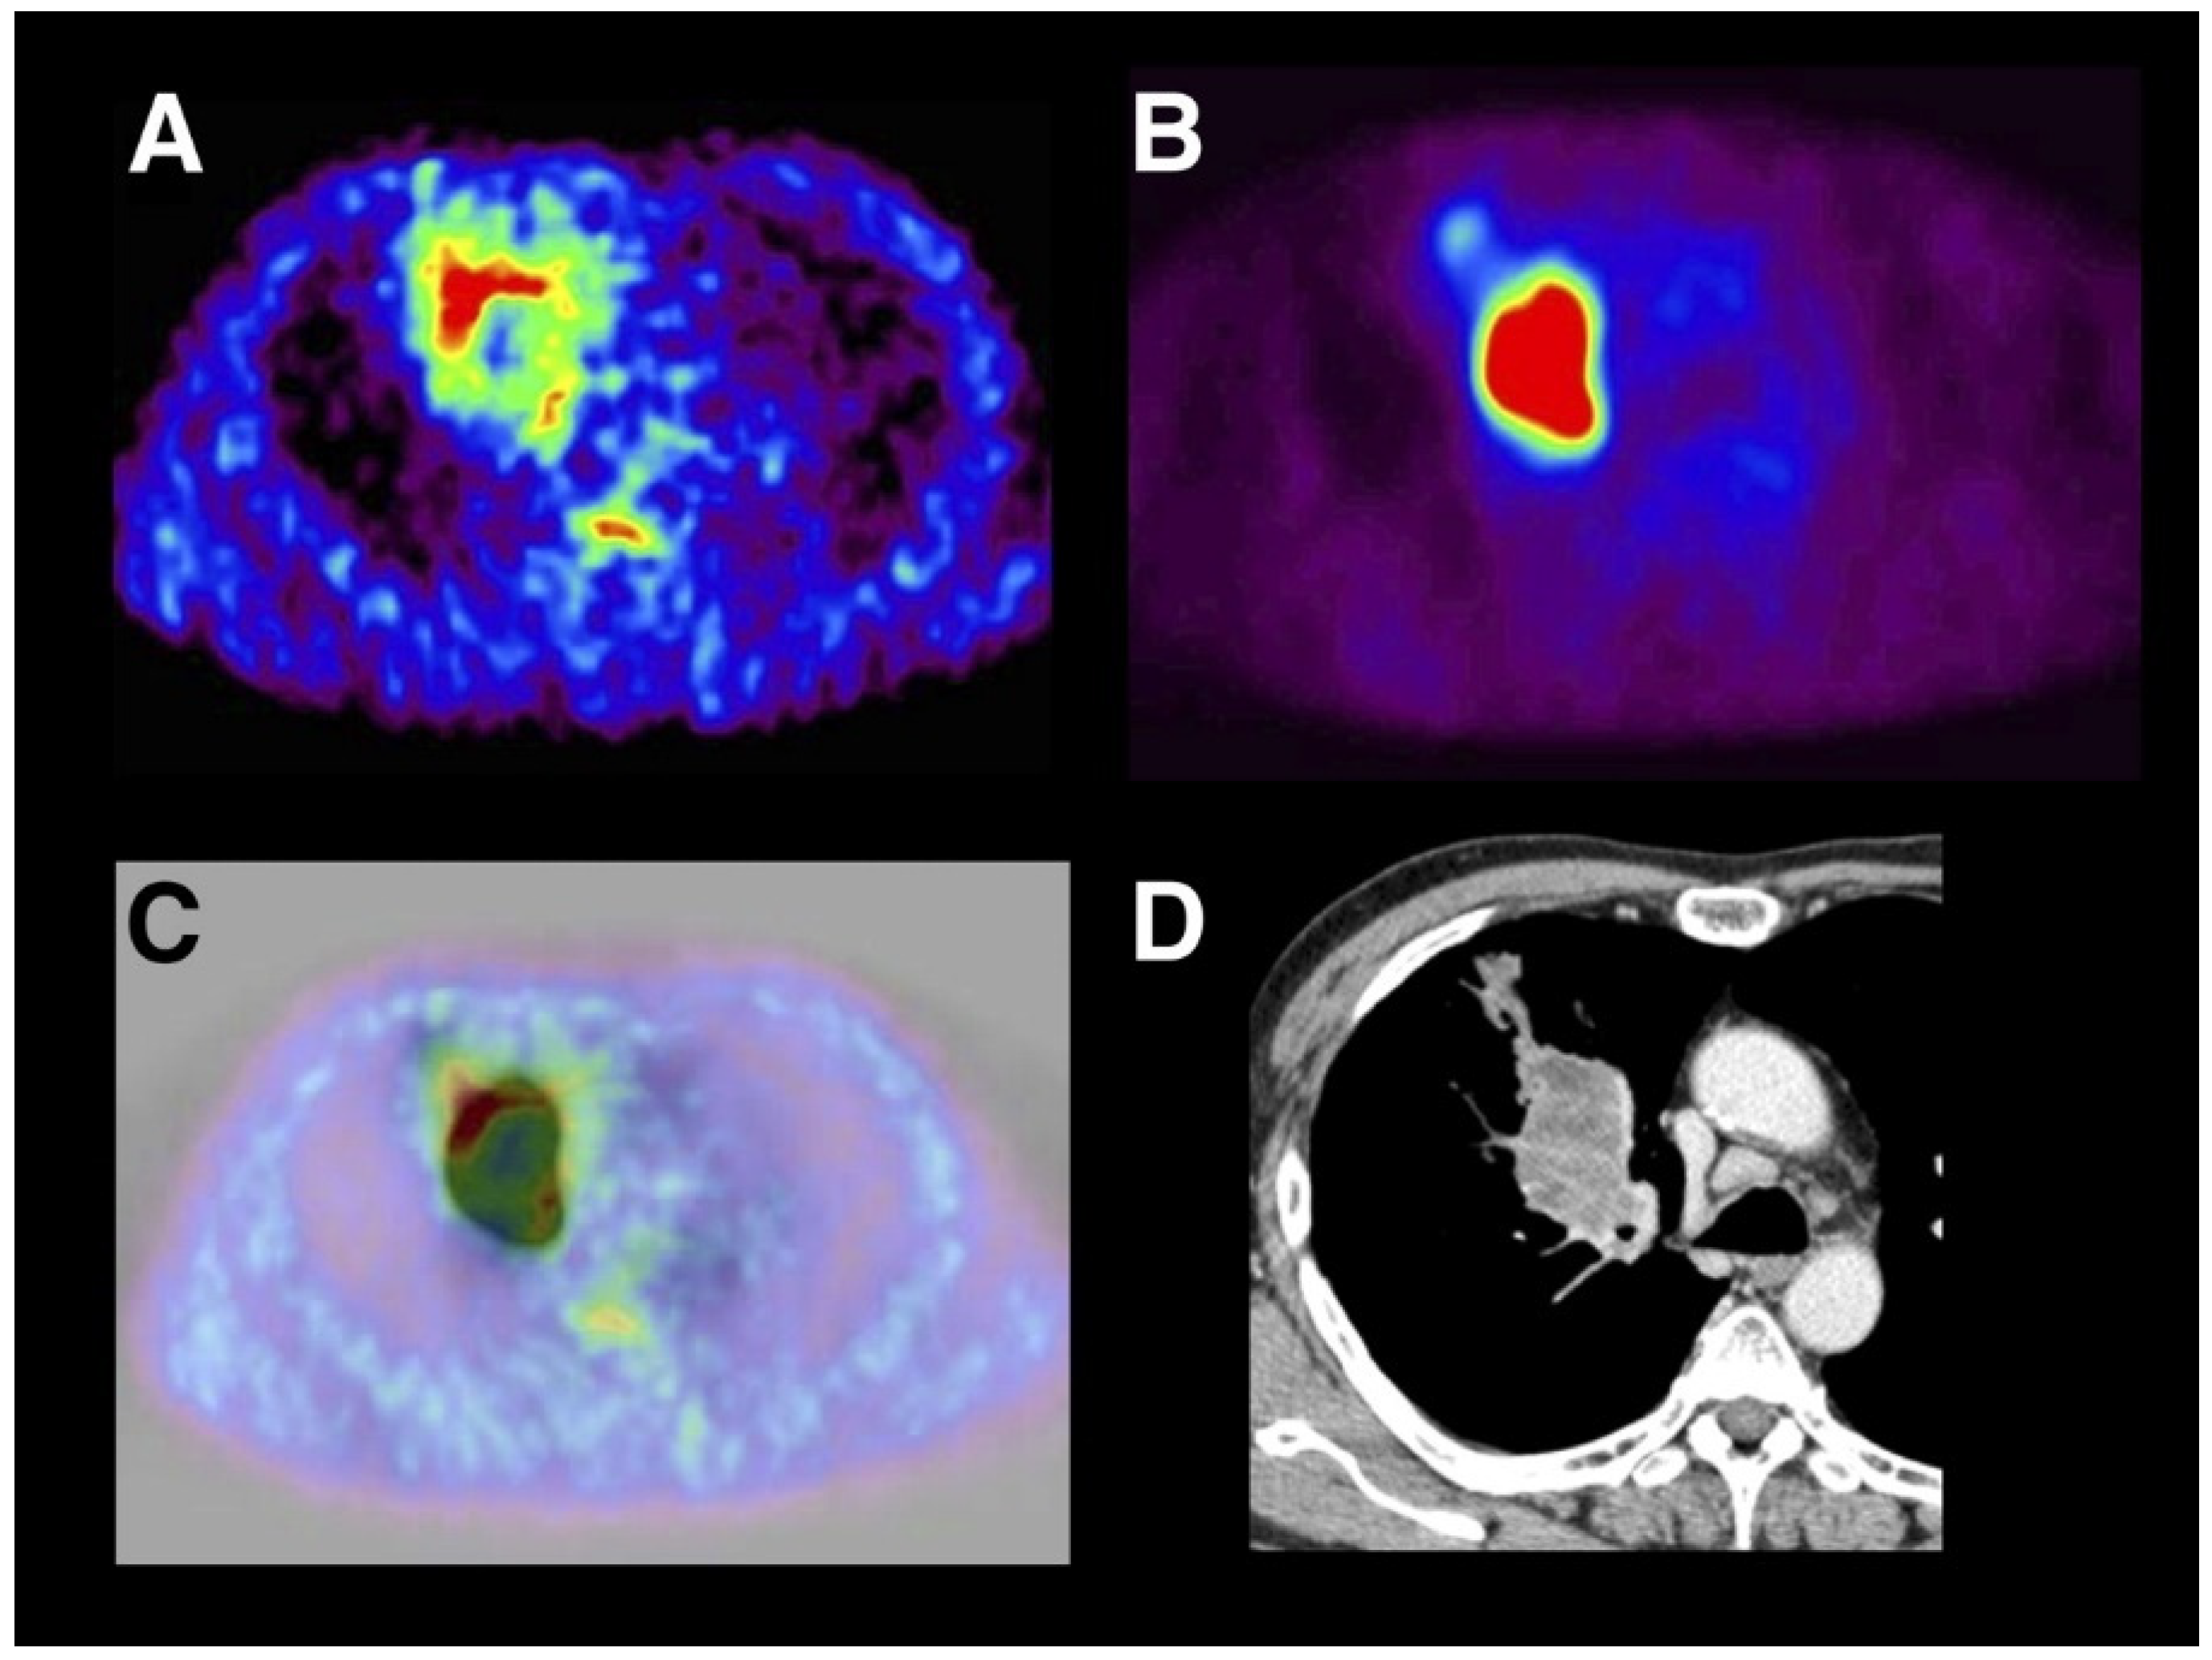

- Watanabe, S.; Inoue, T.; Okamoto, S.; Magota, K.; Takayanagi, A.; Sakakibara-Konishi, J.; Katoh, N.; Hirata, K.; Manabe, O.; Toyonaga, T.; et al. Combination of FDG-PET and FMISO-PET as a treatment strategy for patients undergoing early-stage NSCLC stereotactic radiotherapy. EJNMMI Res. 2019, 9, 104. [Google Scholar] [CrossRef]